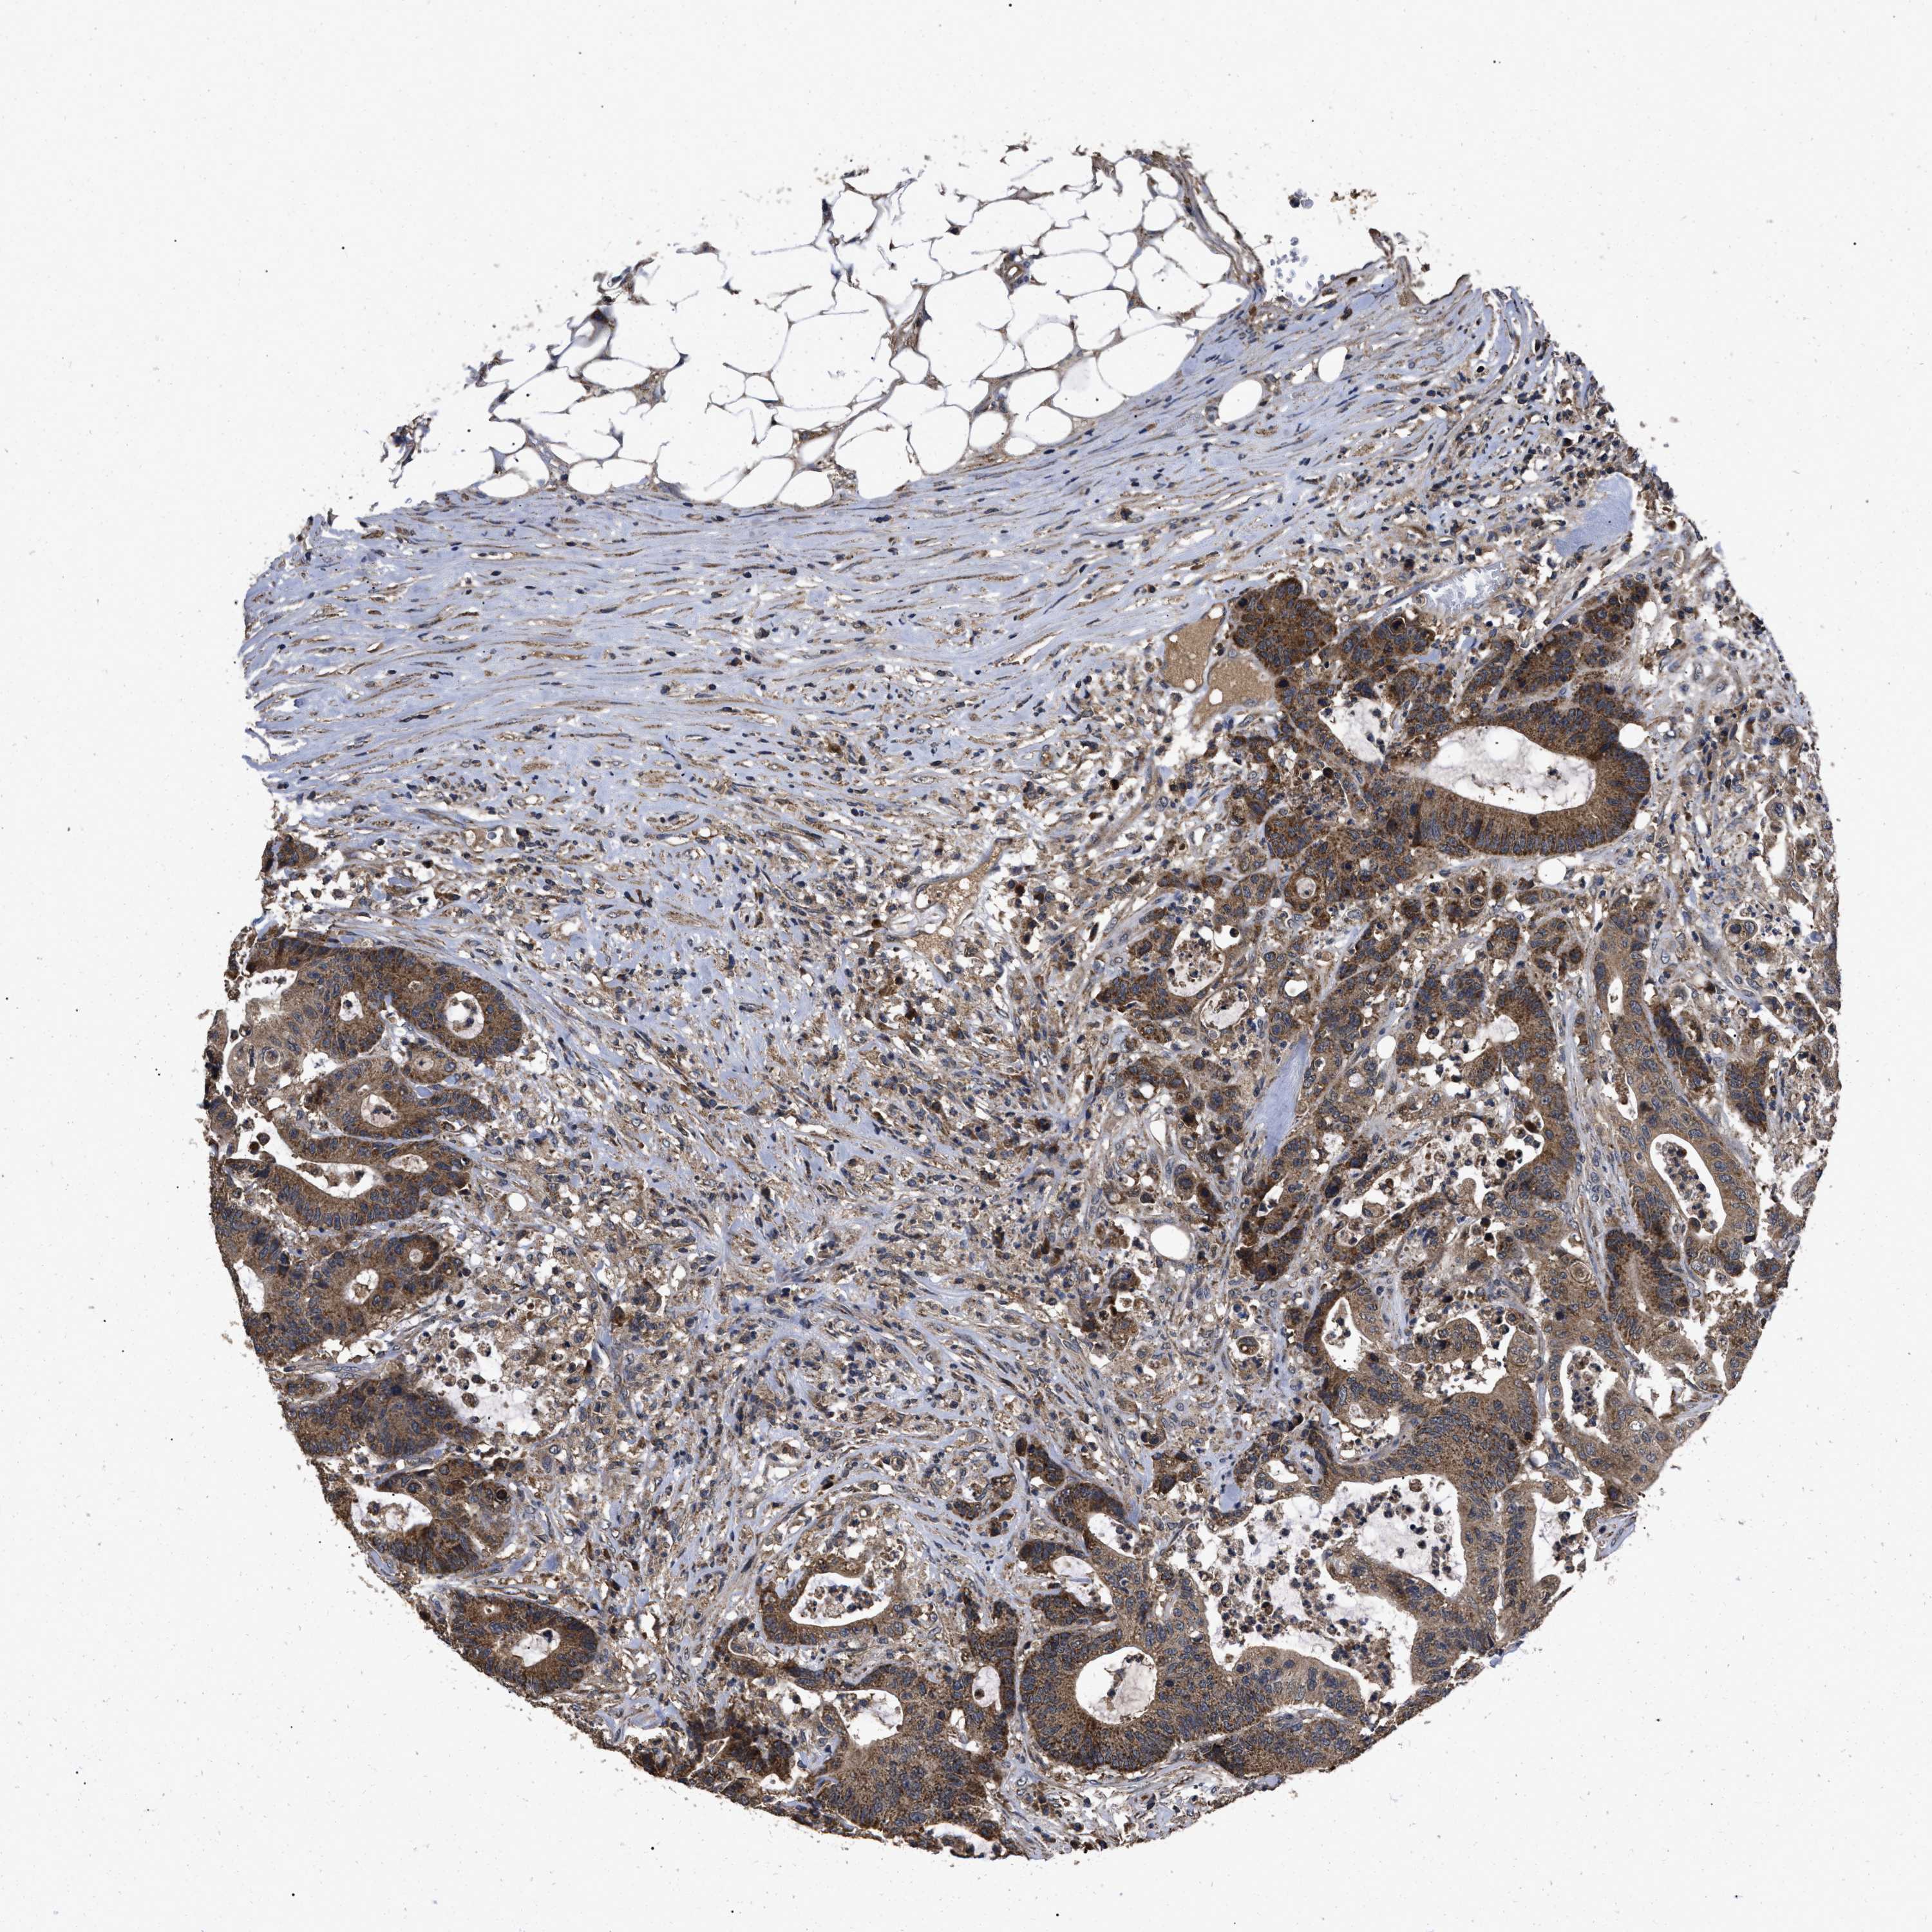

Colorectal cancer

Colon adenocarcinoma